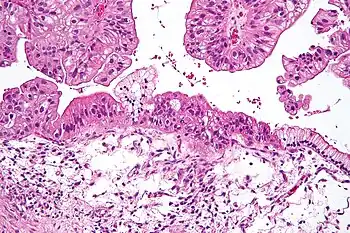

Intermediate magnification micrograph of a low malignant potential (LMP) mucinous ovarian tumour. H&E stain.

The micrograph shows:

Simple mucinous epithelium (right) and mucinous epithelium that pseudo-stratifies (left - diagnostic of a LMP tumour).

Epithelium in a frond-like architecture is seen at the top of image.